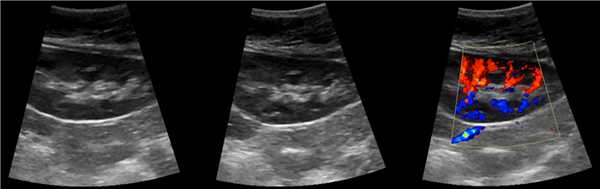

3. КТ при бертиниевых колоннах почки:

• Бесконтрастная КТ:

о Связаны с корковым веществом

о Боковое вдавление синуса почки

о Деформированные смежные чашечки и воронка

• КТ с контрастированием:

о Отсутствие объемного образования

о Контрастирование аналогично нормальному корковому веществу:

- Лучшая визуализация в кортико-медуллярную фазу

- При недостаточной информативности аксиальной проекции эффективна коронарная реконструкция

(Слева) На рисунке показано объемное расширение коркового вещества почки между верхней и средней чашечками.

(Справа) КТ, аксиальная проекция, кортико-медуллярная фаза контрастирования: дорсальная половина межполюсной области почки, контрастируемая аналогично корковому веществу почки. На последующих фазах выявлено гомогенное контрастирование почки.